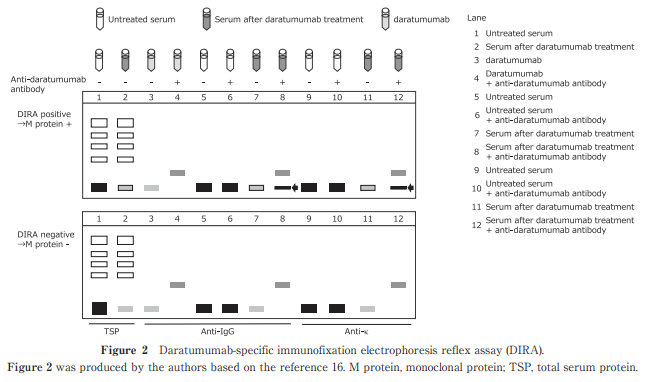

Progress of Therapeutic Antibodies in the Treatment of Patients with Multiple Myeloma and Possible Impacts of Antibodies on the Evaluation of Response to the Treatment

Yoichi Imai et al.

Published online : December 26 , 2024